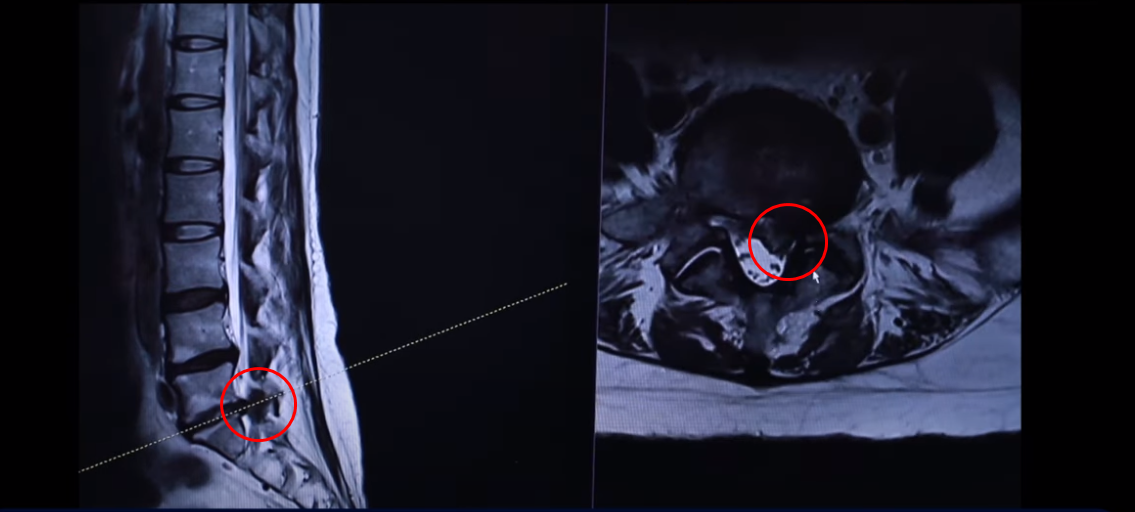

43세 여자 허리 디스크 파열 환자분 MRI 보도록 하겠습니다. 이분은 파열이 어마어마하게 심합니다. 세 마디에 퇴행성 디스크가 있는데 5번 1번을 보면 위와 아래로 밀려 올라가 있죠.

터져서 밀려나온 디스크 수핵이 위와 아래로 밀려 나가 있습니다. 보시면 이쪽이 왼쪽입니다. 환자의 왼쪽을 완전히 덮어버렸죠.

그래서 역시 이분 증상은 왼쪽 다리 방사통입니다. 왼쪽 다리 방사통과 왼쪽 다리 마비 증상 운동 마비는 심하지 않고 감각 마비가 심합니다. 발가락 발바닥 이런 데 감각을 느끼지 못하는 감각 마비 증상이 있습니다. 사실은 이 정도면 운동 마비도 있을 만한데 예를 들면 까치발이 안 된다든가 아니면 족하수 증상이 있다든가. 그런데 그런 운동마비 증상은 없으셨습니다. 너무너무 많이 터졌기 때문에 수술 병원에 가서 즉시 전신 마취를 해서 수술을 해야 된다고 듣습니다.

다시 동생분 MRI로 돌아가겠습니다. 언니분하고 똑같이 이 동생분 세 마디 디스크가 퇴행돼 있죠 그리고 마지막 마디가 터져서 이렇게 왼쪽으로 심하게 밀려 나가 있습니다.

언니분보다 터진 정도는 더 심합니다. 그래서 이렇게 디스크가 심하게 파열되고 또 마비 증상까지 있는 분들 이런 분들은 이 환자분이 들으신 것처럼 정형외과나 신경외과에서 즉시 수술을 해야 된다. 또 마비 증상까지 있으니까 바로 수술을 하지 않으면 마비 증상이 오래되면 신경이 심하게 눌려 있으면 신경 기능이 많이 떨어지면 만약 마비가 풀리지 않는다고 그러면 그건 이제 장애가 되는 거죠. 그렇기 때문에 즉시 수술을 해야 된다 이렇게 듣는데 이렇게 파열이 심한 분들일수록 저희는 오히려 비수술 재활 치료가 성공할 확률이 더 높다. 역설적이게도 파열이 심하면 심할수록 치료가 더 잘될 확률이 높다. 저희 모커리한방병원이 이렇게 설명을 하고 있는데 왜 그럴까요?